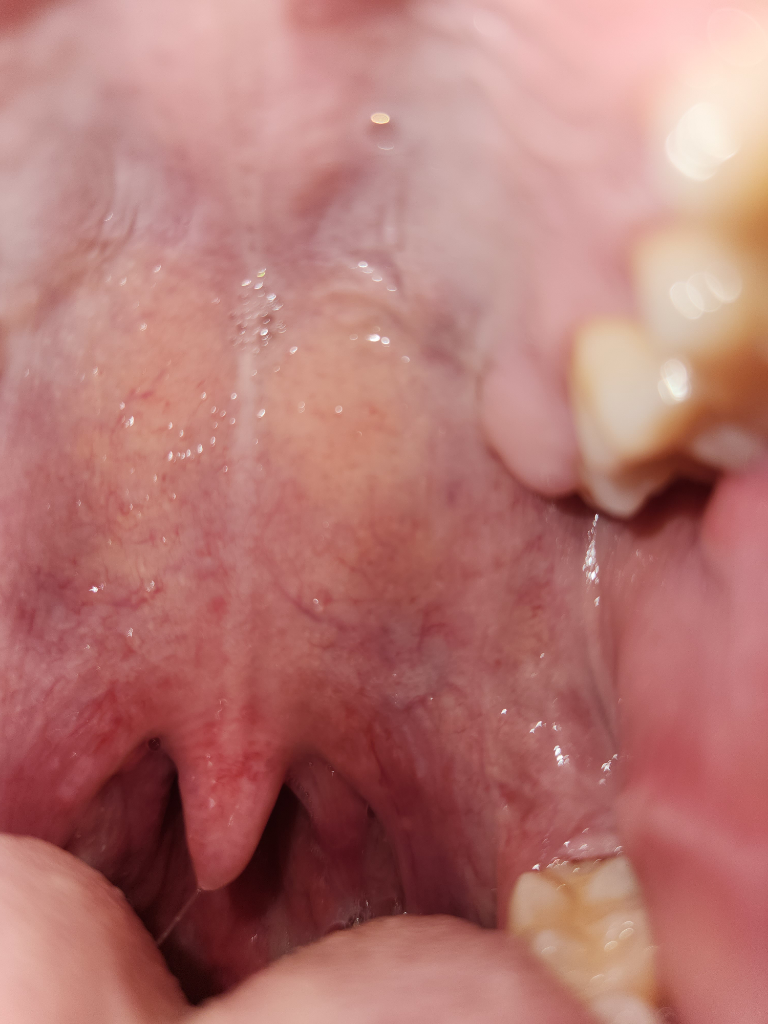

목 안이 아프셔서 불편하시군요.

인후통은 보통 상기도 감염(감기)으로 인한 염증으로 생기는 증상입니다.

감기, 독감, 코로나에서 공통적으로 생길 수 있는 증상이며, 세균성 편도염일 때도 생기는 증상입니다.

대부분은 소염진통제를 복용하면서 경과를 지켜보면 좋아지지만, 증상이 심하면서 고열이 동반된다면 세균성 편도염의 가능성을 고려해 항생제를 복용해야 할 수도 있습니다.